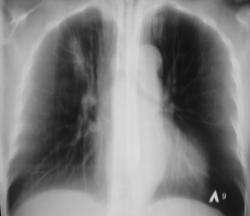

Иллюстрации 1, 2. Произведена рентгенография органов грудной полости в прямой стандартной и правой боковой проекциях. Справа на уровне 1 межреберья дифференцируется крупноочаговая тень овальной формы, от которой в сторону костальной плевры прослеживается линейный тяж. Справа регистрируется усиление и обогащение легочного рисунка. Рисунок правого корня усилен, обогащен, тень его несколько расширена.